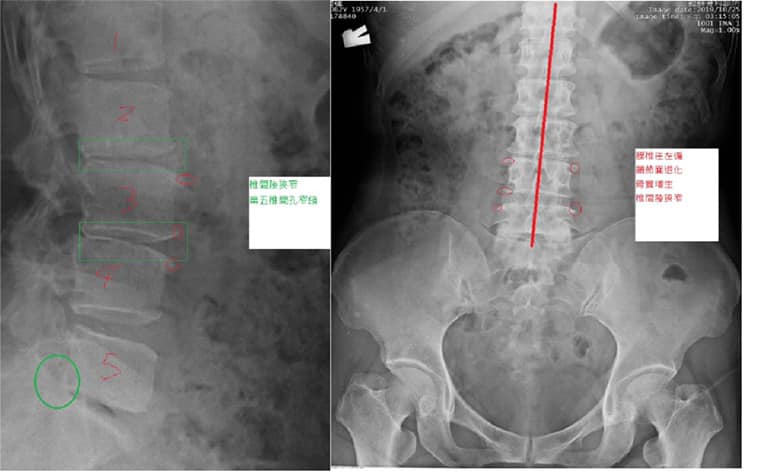

Cervical Spine Treatment Cases 腰椎治療案例 史上超多內心小劇情醫案文章請耐心看完 辛苦的貨車司機腰椎辛酸血淚史 各式各樣治療都... 2020.04.24 感謝台中后里區鍾小姐熱情見證 車禍後導致椎間盤突出 痛到懷疑人生原本考慮開刀治療 ... 2020.04.16 #腰椎滑脫合併椎管狹窄醫案 #脊椎整合中醫微創逆轉勝 #老人家不可以跌倒不可以跌到 #... 2020.04.11 #搬重物閃到腰受傷一痛就痛兩年 #復健許久沒效拍攝核磁共振才知道椎間盤突出 #脊椎整... 2020.04.10 #抱狗閃到腰居然痛麻到不行快半年 #原來是椎間盤突出啊 #脊椎整合中醫微創逆轉勝 2020.04.03 #腰椎滑脫逆轉勝醫案 #曾經大痛到一個月無法走路居家臥床 #原本認真考慮接受骨科融合... 2020.03.31 #腰椎輕微滑脫醫案 #感謝桃園八德蔡阿姨熱情見證 #脊椎整合中醫微創 2020.03.20 腰痛到小腿一直麻痛是怎麼回事 腰椎第四第五椎間盤突出惹禍 打噴嚏跟咳嗽都超痛的 脊... 2020.03.11 #腰椎明顯滑脫醫案 #感謝三重蔡先生熱情見證 #曾經大痛到無法工作跟無法睡覺 #脊椎整... 2020.03.07 #感謝雲林李阿姨熱情見證 #腰椎滑脫合併椎管狹窄 #脊椎整合中醫微創療法逆轉勝 2020.03.01 曾經腰痛連大腿小腿到無法睡覺 大醫院核磁共振檢查後證實椎間盤突出 四個多月的疼痛原... 2020.03.05 #跨國治療台灣醫療奇蹟 #遠從澳洲坐飛機回台專門接受治療 #台灣中醫脊椎整合微創療法... 2020.01.17 #兒子老婆陪同林伯伯一起見證奇蹟 #腰椎滑脫合併椎管狹窄 #治療前走路無法超過五分鐘 ... 2019.12.28 #跨國治療台灣醫療奇蹟 #遠從越南坐飛機專門接受治療 #台灣中醫脊椎整合微創療法立大... 2019.12.26 再度逆轉勝!腰椎治療醫案 原本痛到懷疑人生都想去手術了 八週治療後生路活虎!還可以... 2019.12.18 ← 上一頁 11 12 13 14 15 下一頁 →